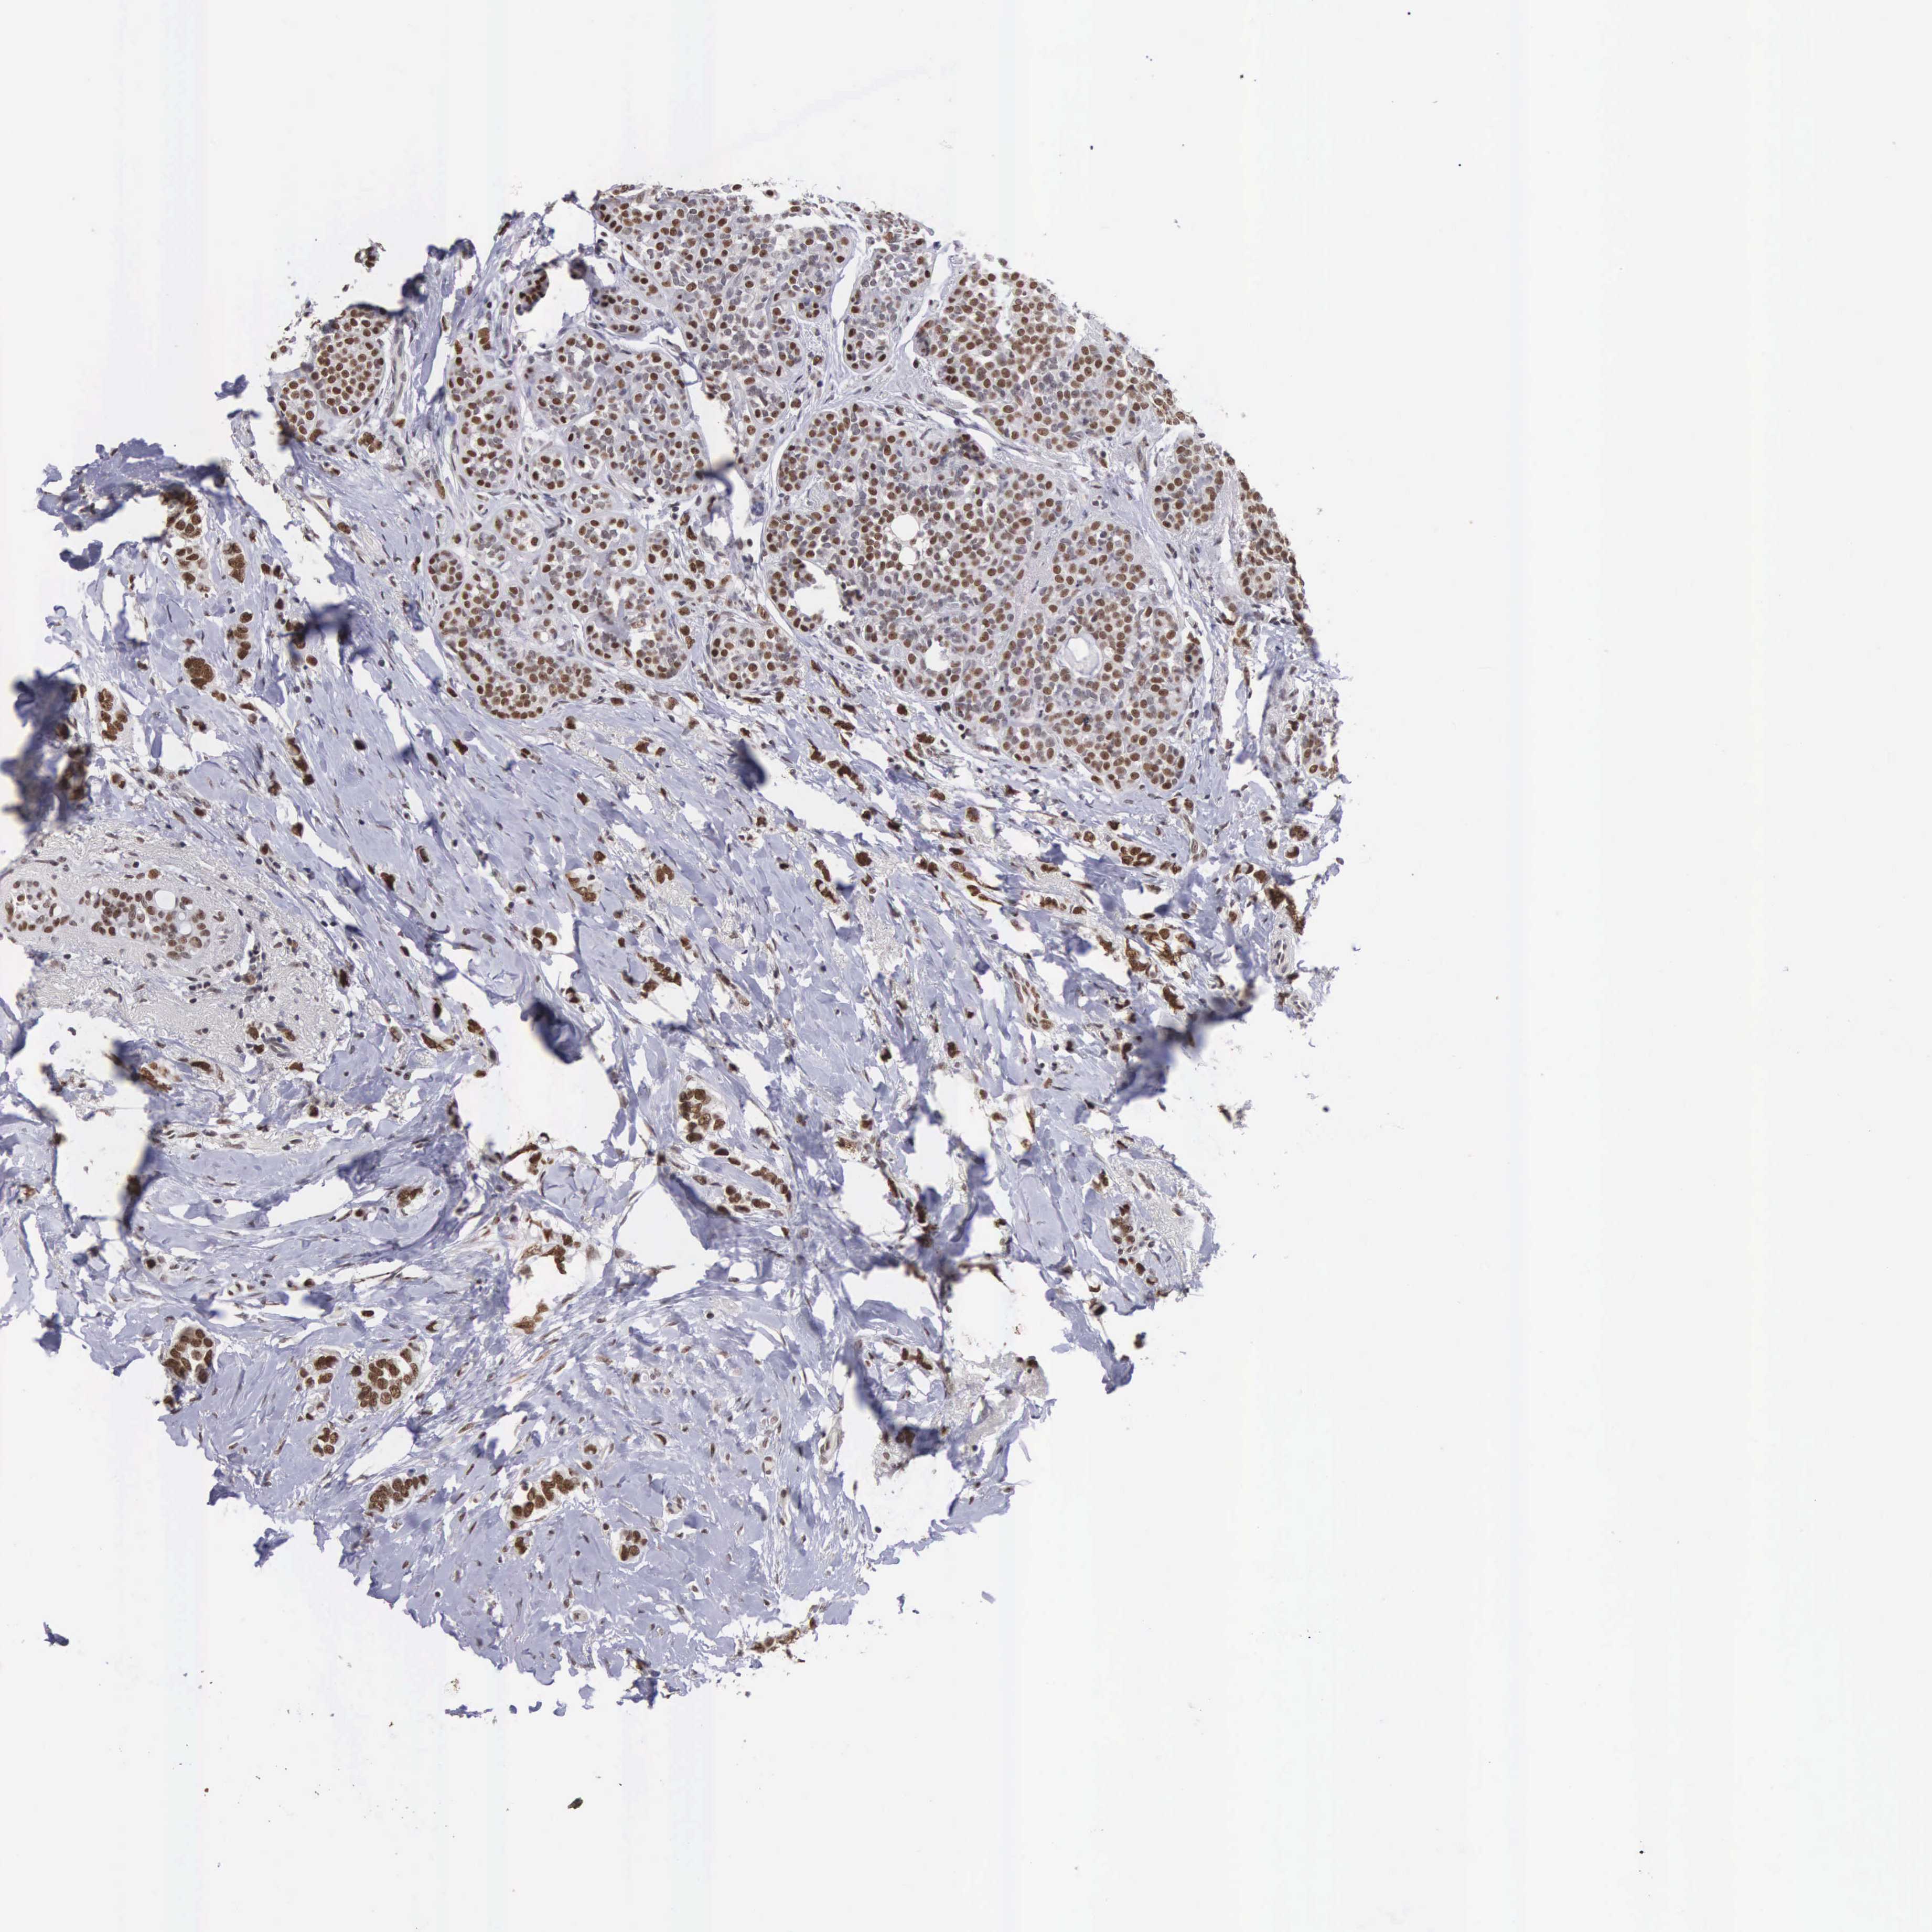

BRCA TCGA BRCA VALIDATION PROTEIN EXPRESSION

ANTIBODIES

AND

VALIDATION